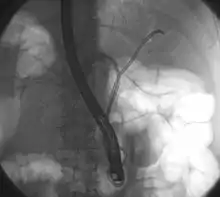

ERCP: stents placed in the left and right bile duct. At the right, the contrast that has been given before is already well-drained, making the bile ducts clearly recognizable.